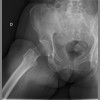

RX CADERA DERECHA

Estudio 250017904631033 de 19/09/2025

cadera der.

RX AMBAS CADERAS (protec.gonadal)

Estudio 250017904631035 de 19/09/2025

cadera(s)